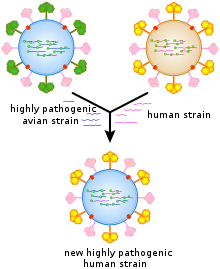

Antigenic shift is a sudden, drastic change in an influenza virus's antigen, usually HA. During antigenic shift, antigenically different strains that infect the same cell can reassort genome segments with each other, producing hybrid progeny. Since all influenza viruses have segmented genomes, all are capable of reassortment.[10][18] Antigenic shift, however, only occurs among influenza viruses of the same genus[19] and most commonly occurs among IAVs. In particular, reassortment is very common in AIVs, creating a large diversity of influenza viruses in birds, but is uncommon in human, equine, and canine lineages.[24] Pigs, bats, and quails have receptors for both mammalian and avian IAVs, so they are potential "mixing vessels" for reassortment.[17] If an animal strain reassorts with a human strain,[2] then a novel strain can emerge that is capable of human-to-human transmission. This has caused pandemics, but only a limited number have occurred, so it is difficult to predict when the next will happen.[1][9]